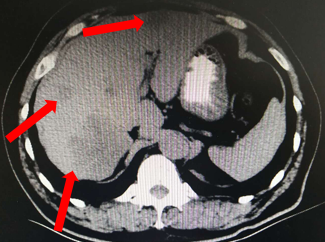

腹部CT(2015.12.14)

肝右叶可见不规则形略低密度影,大小约7.9*6.1cm,其内密度不均匀,局部外突,边缘模糊,肝内可见多个类圆形略低密度灶。直肠壁不规则增厚,局部肠腔变窄,盆腔内未见明确肿大淋巴结。